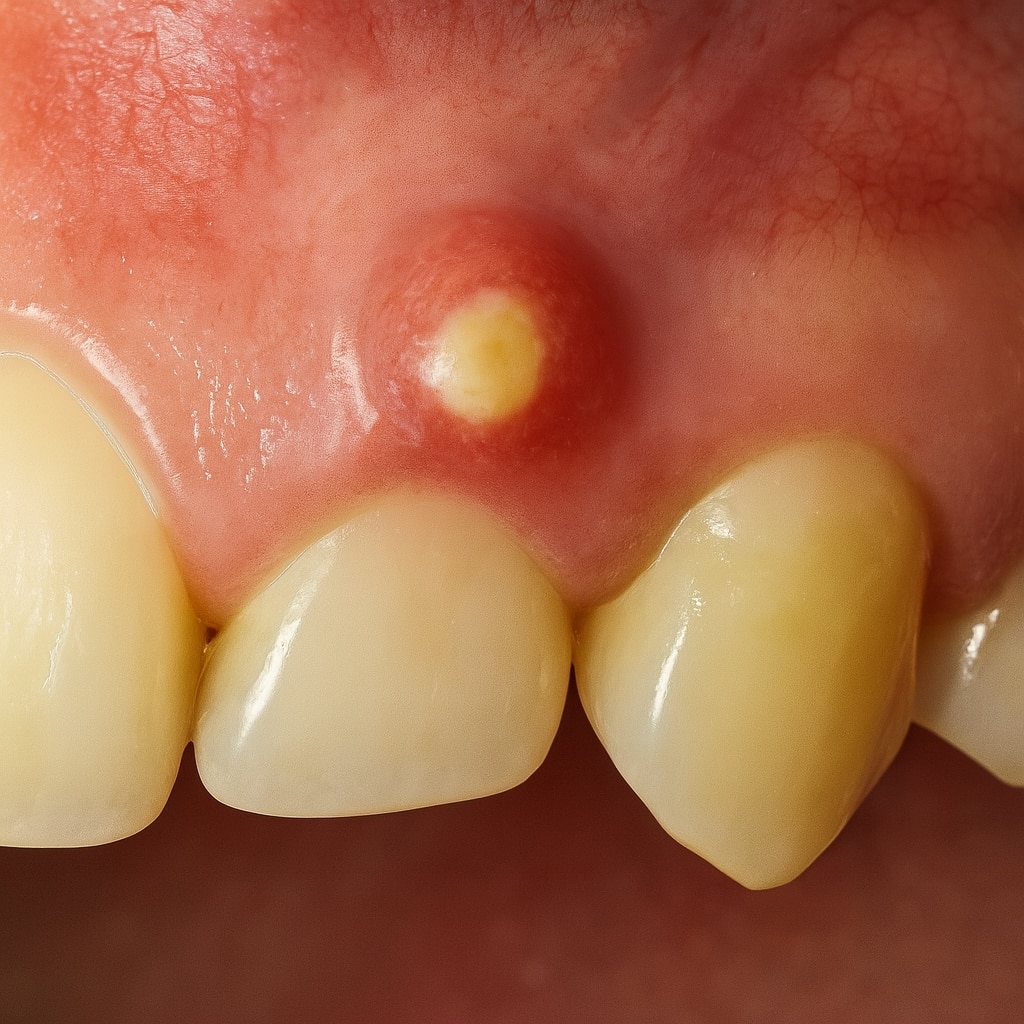

Un absceso dental es una acumulación de pus causada por una infección bacteriana que se localiza en la zona de un diente o en los tejidos que lo rodean. Esta infección puede aparecer por diversas causas y se manifiesta generalmente con dolor, inflamación, mal aliento y, en algunos casos, fiebre.

- Mal sabor de boca o pus visible

Absceso gingival

Se forma en el margen de la encía, normalmente por la acumulación de restos alimenticios o por cuerpos extraños alojados bajo la encía.

Drenaje de un absceso dental

En ciertos casos, será necesario realizar un drenaje profesional para eliminar el pus acumulado. Este procedimiento se realiza en consulta y puede ir acompañado de un tratamiento complementario como la endodoncia o la limpieza profunda, según la gravedad del caso.